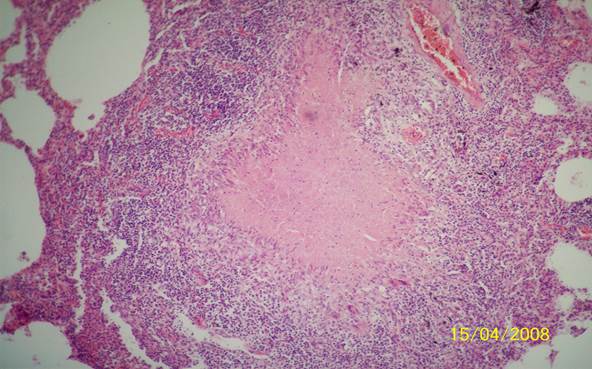

Микроскопический взгляд на мишитарный туберкулез легкого: фотодокументация

Раздел: Снимки-откровения